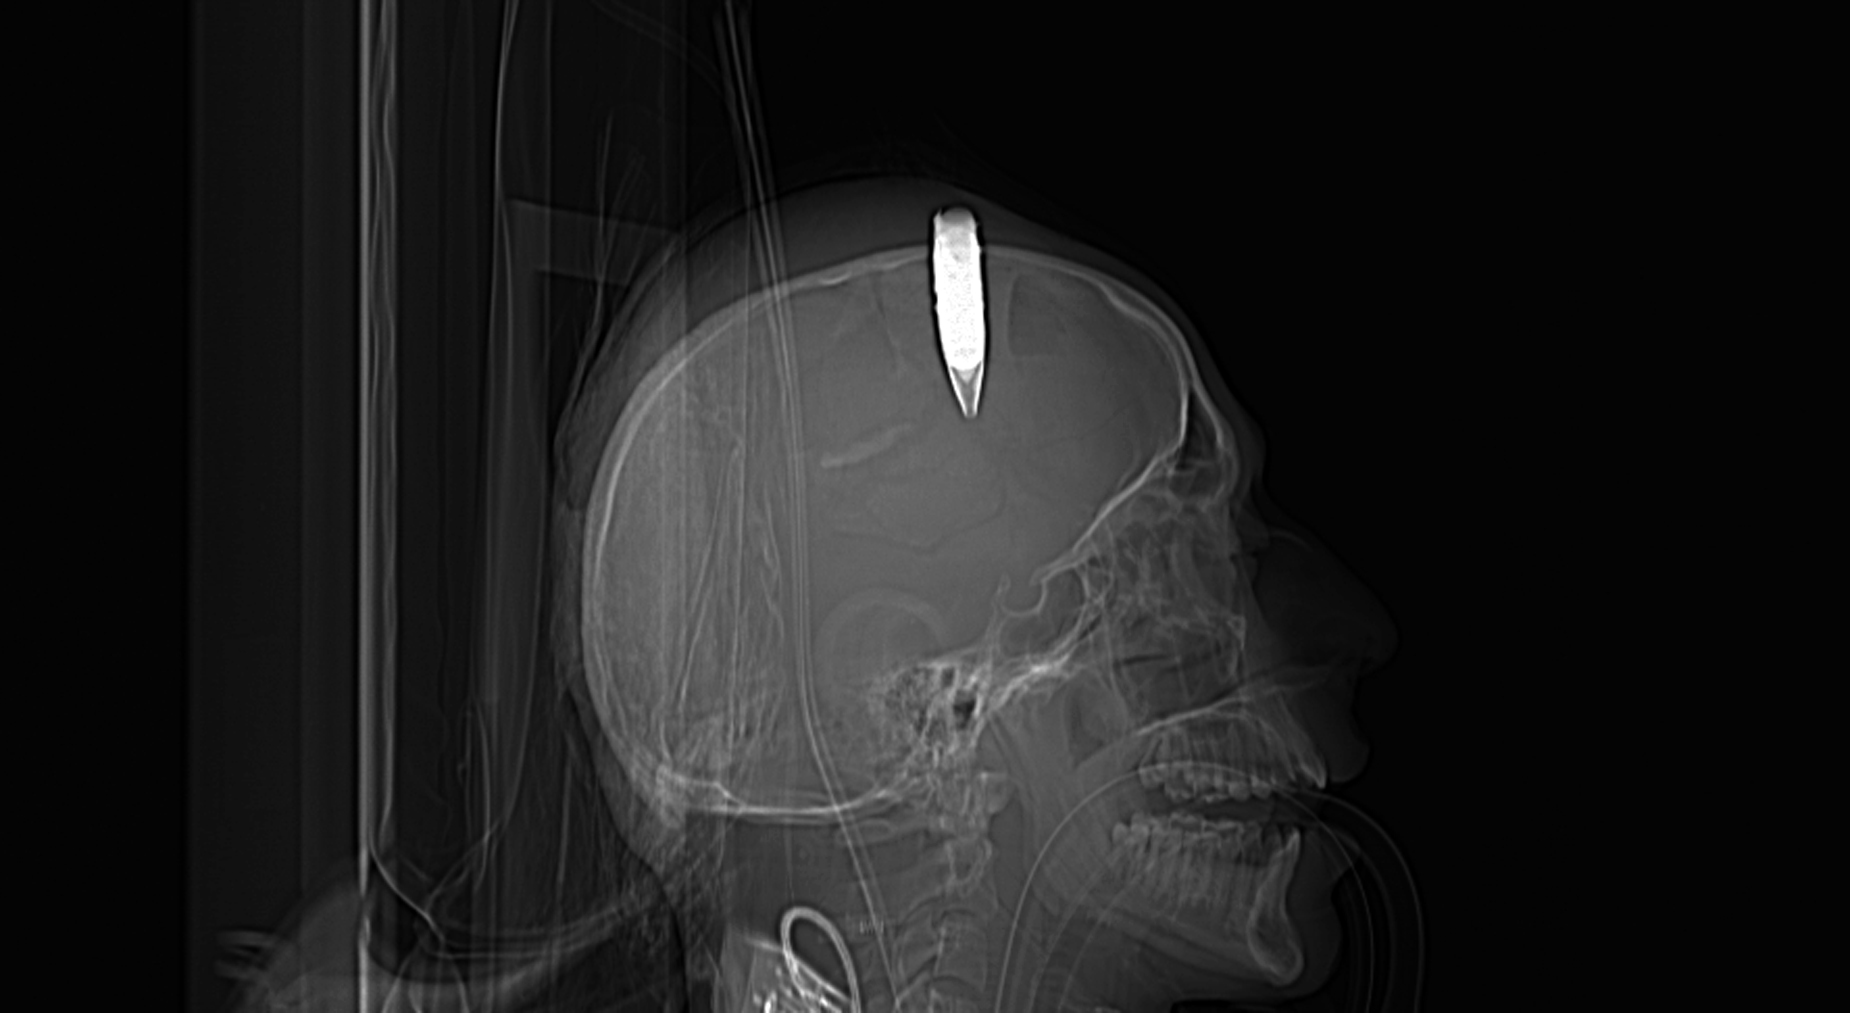

«Да у него пуля в голове. Человек далёкий от футбола, я вообще не понимал, что это за тренер. Где футбол, а где он! Он мог орать, кричать, целовать. Персонаж из какого-то мультфильма. Для меня он просто клоун», – в 2014 году Александр делился впечатлениями с журналистом «Советского спорта».